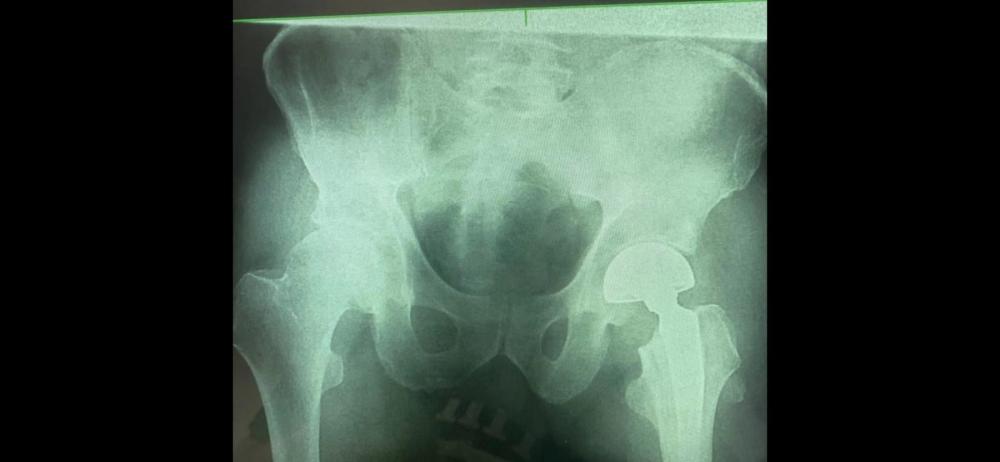

Під час огляду діагностували закритий субкапітальний перелом шийки лівого стегна. Після детально обстеження вибрали тактику лікування - однополюсне цементне протезування лівого стегна.